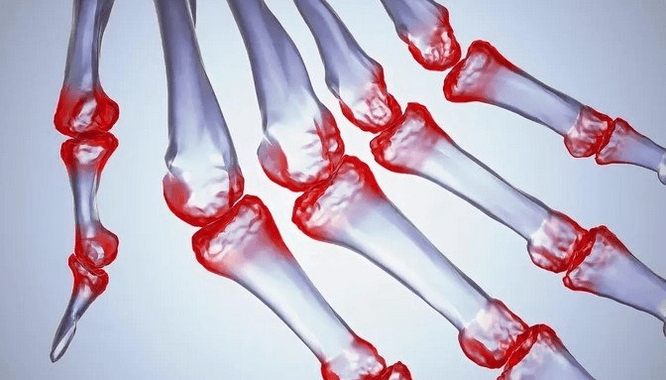

Rheumatoide Arthritis

Rheumatoide Arthritis ist eine Krankheit, bei der das menschliche Immunsystem Körpergewebe schädigt. Mit anderen Worten, rheumatoide Arthritis ist eine Autoimmunpathologie. Diese Krankheit ist auch systemisch, da viele Gewebe betroffen sind (Muskeln, Gelenke, Vasen usw.) und Organe (Herz, Nieren, Lungen usw.) im Körper.

Trotz der Tatsache, dass rheumatoide Arthritis in größerem Maße eine systemische Krankheit ist, leiden die Gelenke, während die Verletzung anderer Gewebe und Organe im Hintergrund liegt. Mit dieser Krankheit können fast alle Arten von Bürsten beeinflusst werden (Zeichnungen aus Handgelenk, Karpalgefahren, Metacarpal-Falan-Gelenke, Inter-Falan). Die Läsion ist im Allgemeinen symmetrisch (diese. Die gleichen Gelenke sind interessiert) an beiden Händen, begleitet von Schwellungen, Schmerzen in beschädigten Gelenken. Am Morgen, während des Hebens aus dem Bett, gibt es in den betroffenen Gelenken ein wenig Starrheit, die etwa 1 Stunde dauern und dann spurlos verschwinden können.

Sehr oft mit rheumatischer Arthritis in der Nähe der betroffenen Gelenke der Bürste (Häufiger die Articop-Falan-Gelenke, Schnittstellen) Rheumatoide Knötchen erscheinen. Sie sind eine abgerundete Formation, die sich unter der Haut befindet. Auf dem Pinsel entstehen diese Formationen häufiger auf der Rückseite. Bei Palpation sind sie dicht, inaktiv und schmerzlos. Die Anzahl von ihnen kann variieren.